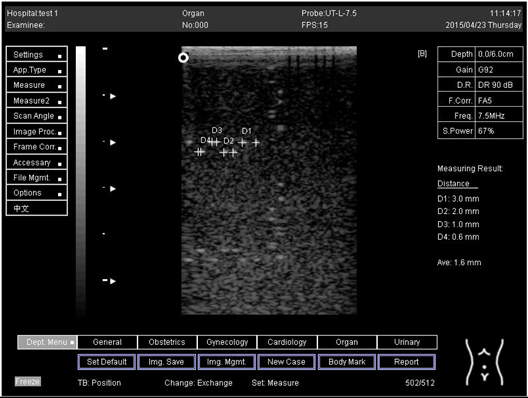

Table A7. The image taken for focal zone determination in different depth using linear probe on phantom 2.

Depth (cm)Diagram

5.0Biomimetics 07 00130 i037

6.0Biomimetics 07 00130 i038